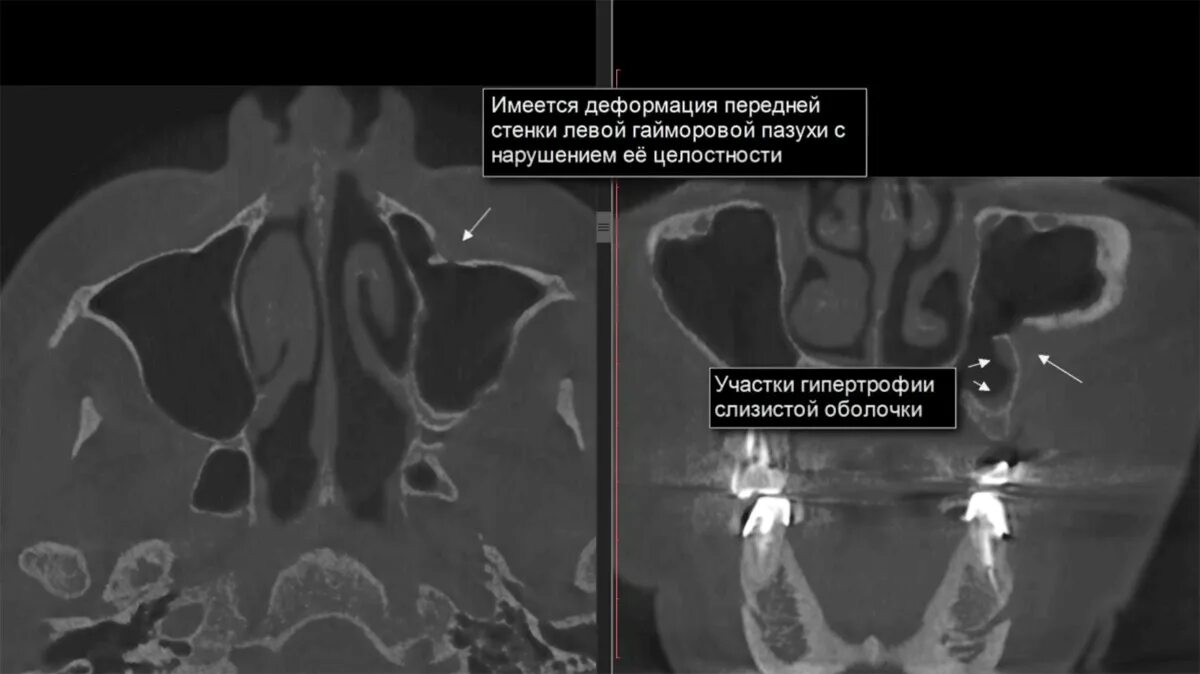

Утолщение верхнечелюстной пазухи что это значит